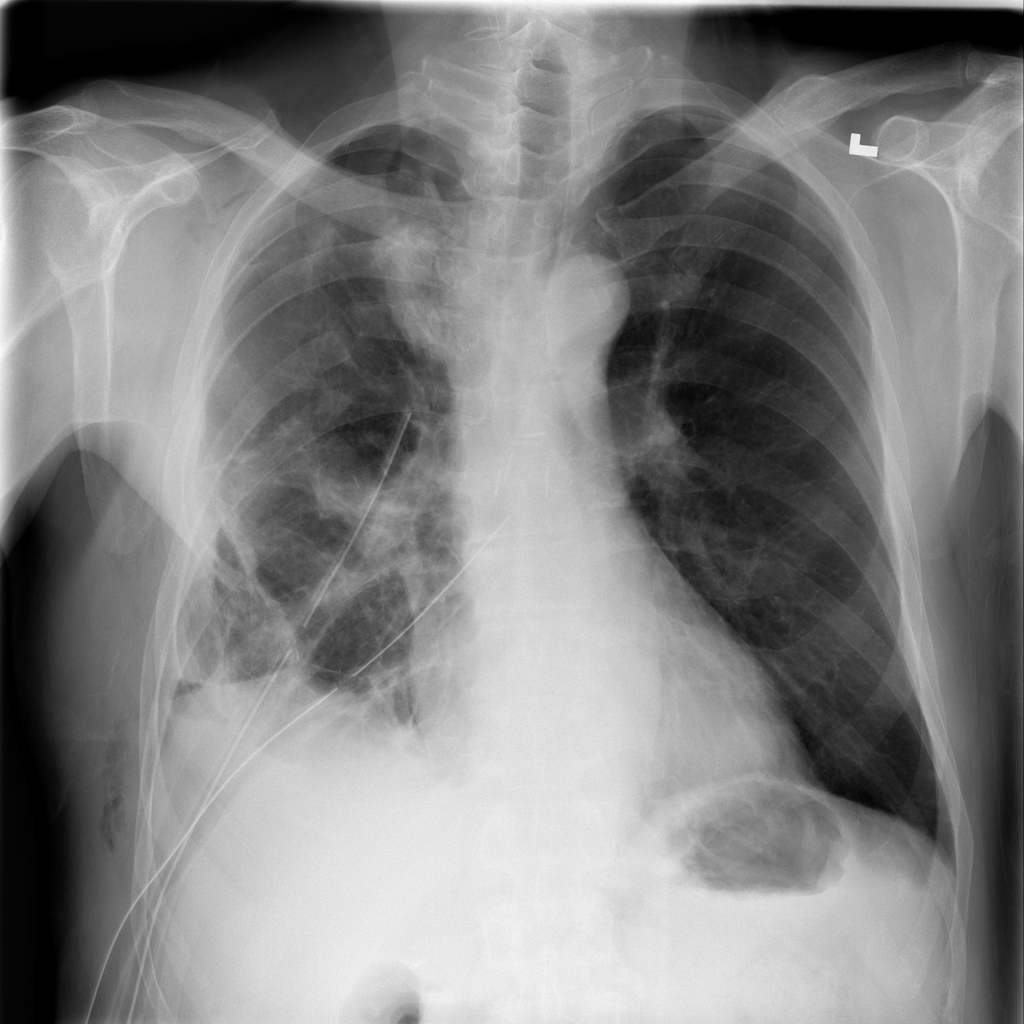

Showing up to 90 reference images for Pneumothorax.

PAT-2CA6 · IMG-004Pneumothorax

PAT-2CA6 · IMG-004

PA